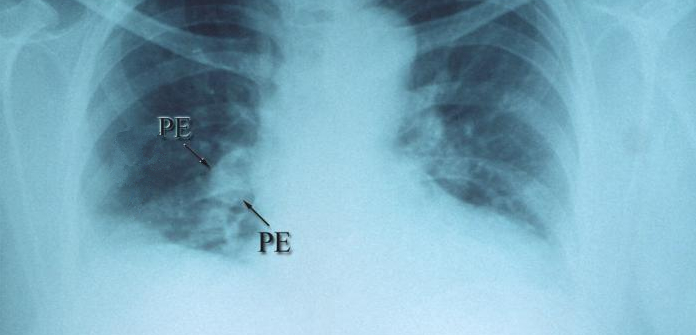

Thrombolytics Reduce Pulmonary Embolism Deaths by 47%

Adding thrombolytic drugs to conventional therapy may offer significant benefits for patients with intermediate-risk sudden-onset pulmonary embolism (PE), according to a new meta-analysis in the Journal of the American Medical Association.

Adding these clot-busting medications to standard treatment was associated with 47% fewer deaths than using standard anticoagulant therapy.